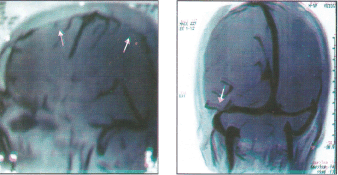

Rana et al., 1978 (10) investigated 108 cases of ischemic strokes in young soldiers, below 45 years of age. Twenty three (21.3%) patients had onset at high altitude while serving above 3500 meters. One (4.3%) patient gave history of HAPE while another patient, a local resident of high altitude area, had pulmonary hypertension. One (4.3%) patient had ischemic stroke in the past from he had recovered fully. Thirteen (56.5%) patients were smokers. No evident source of embolism was detected. There was no relation to duration of stay or number of induction to high altitude. None had other features of other high altitude illness at the onset of stroke. As a group their hemoglobin range from 14–15 gm/dl (mean 14.8.gm/dl) and hematocrit value were 36–49%. Platelet adhesiveness and plasma fibrinogen was increased while fibrinolytic activity was reduced suggesting a hypercoagulable state and was presumed to be the cause as all patients were young and lacked risk factors except smoking and stay at high altitude. All the patients were evacuated to plains and treated with asprin 300 mg twice a day. Six (26.08%) cases angiographic abnormalities which included proximal internal carotid artery (ICA) block in 2(8.6%), middle cerebral artery (MCA) block in 2(8.6%), hypoplasia of ICA and tortuosity of intracranial vessels (Figure 1 & 2) in one (4.3%) case each respectively. Initially development of tortuosity was thought akin to the development of tortuosity of ophthalmic arteries at high altitude. However, when angiographic abnormalities in 108 cases were reviewed this abnormality was noted in 11.1% of cases (15). Follow up 108 cases (16) revealed a mortality rate of 4.4%. While 63% were independent, 10.1% needed supervision only, 32.2% needed assistance and 2.2% were dependant for acts of daily living respectively. All the 23 patients with onset of stroke at high altitude recovered and could be rehabilated back to their parent jobs. The patient with tortuosity of intracranial vessels (Figure-1) and 4 years later presented as CP angle tumor (Figure-2).

Figure-1: Carotid angiogram showing marked toruosity of intracranial vessels

Figure-2: CT scan of the same patient done after 4 years showing tortuous vessels presenting as cerebello-pontine angle (CPA) tumor